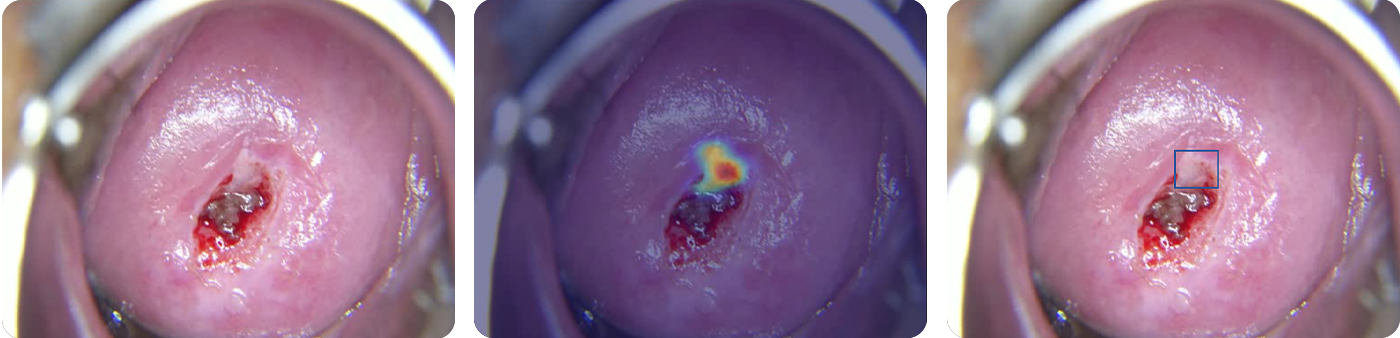

Cerviray AI

CIN2-3